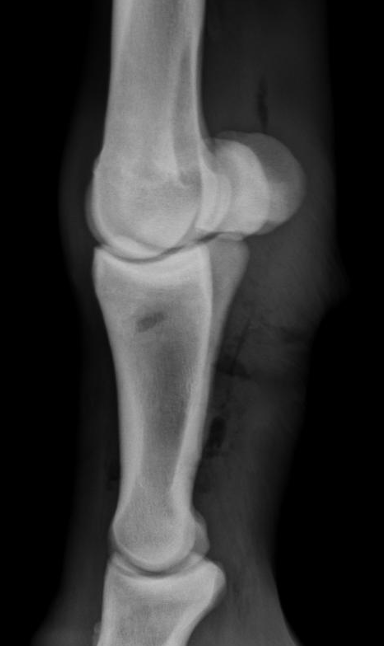

What is shown in these radiographs?

A

dystrophic mineralization at the level of an elbow joint repair